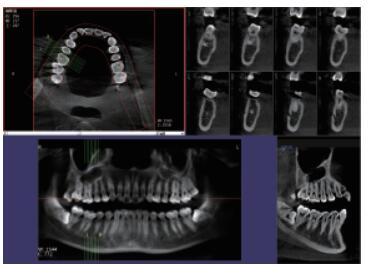

三維重建任意斷層

專有三維重建算法,可提供任意位置高清斷層影像。

高清口腔全景影像

通過三維容積影像,提取高清口腔全景影像。

多平面組合重建

可同時(shí)觀察軸向面、冠狀面和矢狀面圖像,方便臨床診斷。